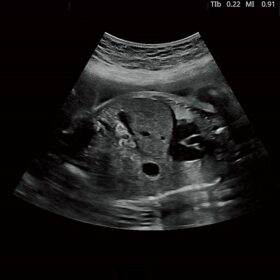

FUTUS features great imaging technologies to support a clear view and confident diagnoses.